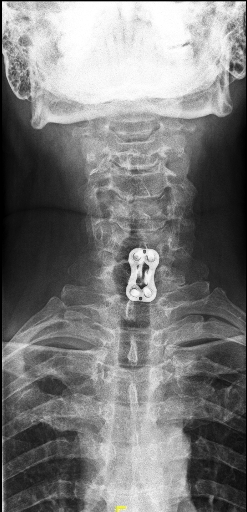

Las RX dinámicas (6m postop) demuestran estabilidad de la artrodesis

Rx AP donde se aprecia la placa y la caja lateralizada a la izquierda